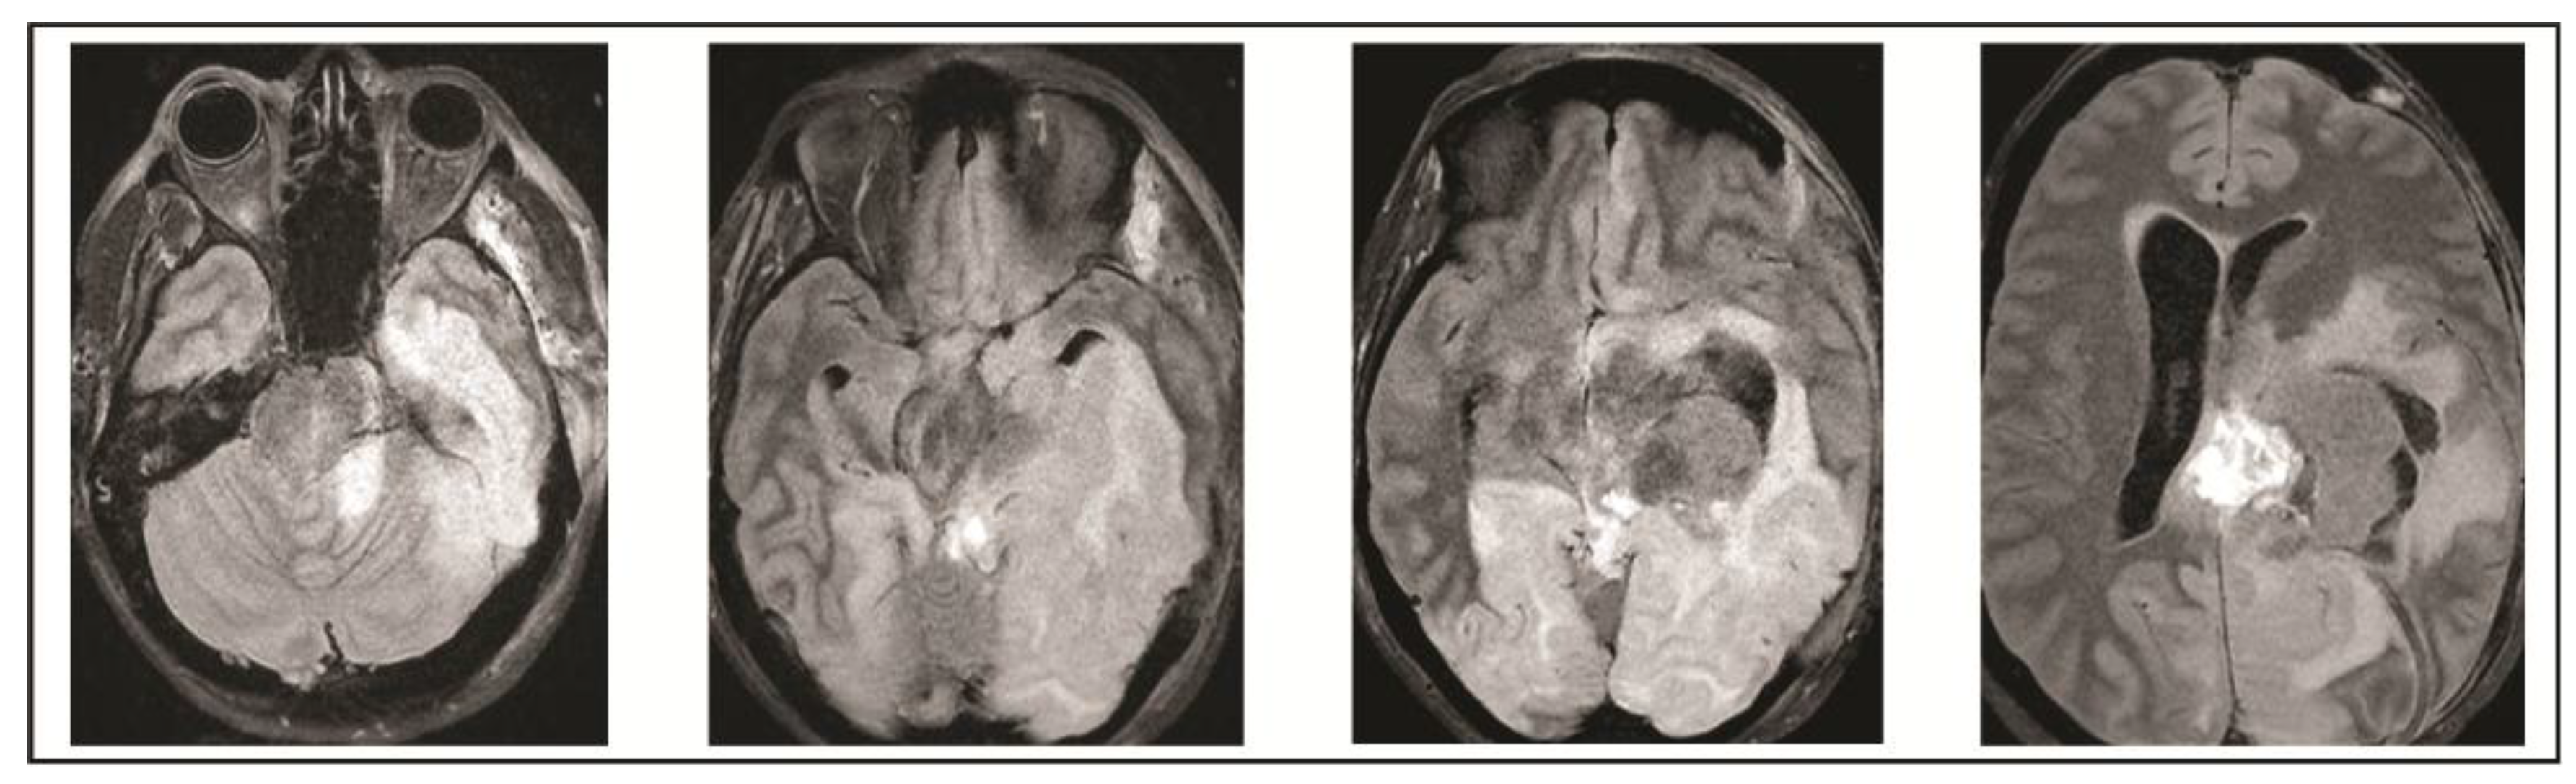

2. Case Presentation